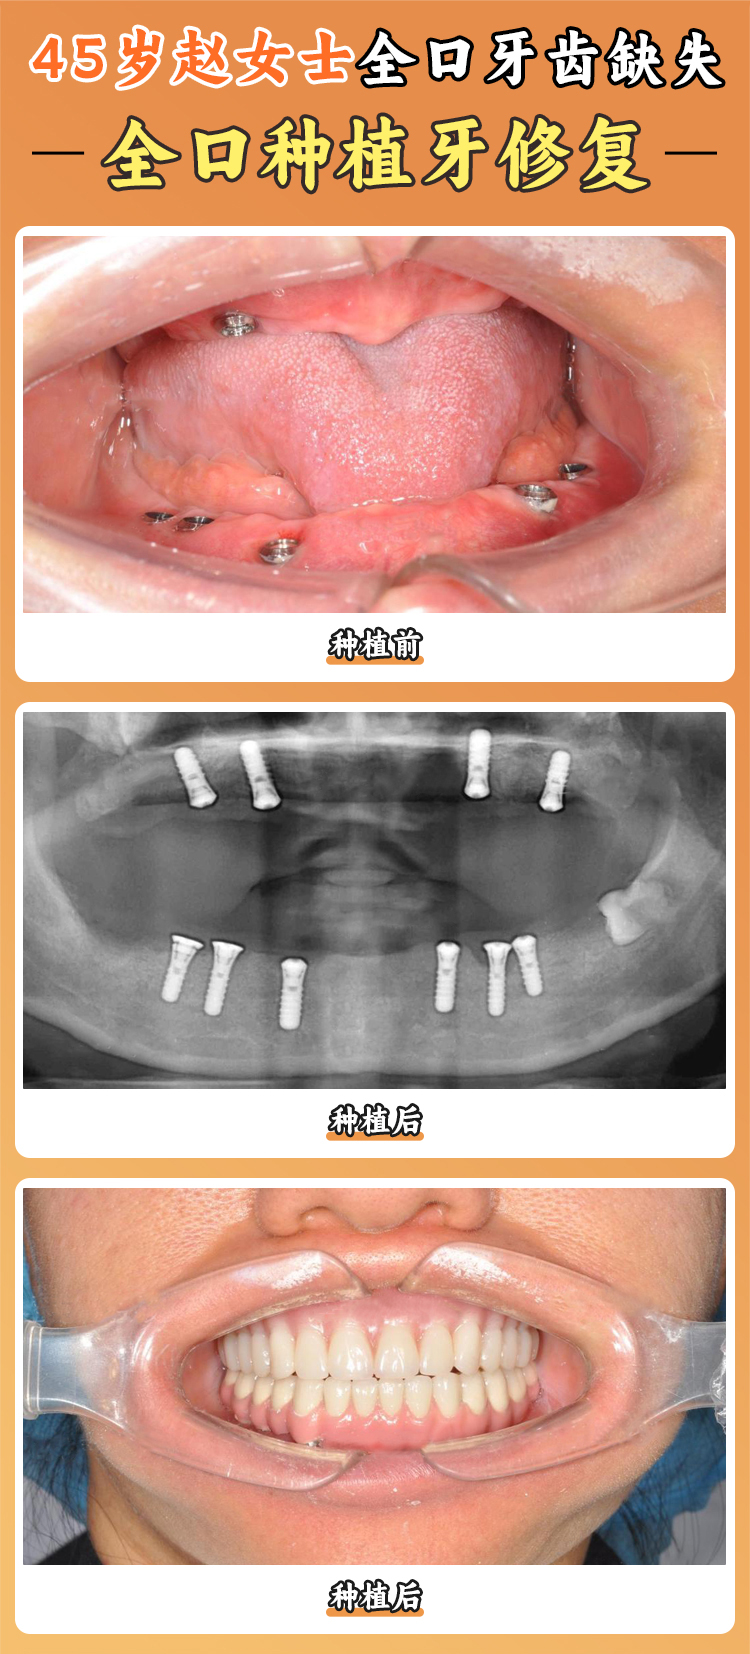

全口種植牙方面:

- 全口半固定種植4萬元起,經(jīng)濟(jì)實(shí)用,清潔方便,適合老年患者。

- 微創(chuàng)全口種植5萬元起,借助3D導(dǎo)板定位,創(chuàng)傷小、修復(fù)快。

- All - on - 4全口種植6萬元起,4顆種植體撐起全口牙橋,無需大面積植骨。

- All - on - 6全口種植7萬元起,6顆種植體支撐力均衡。

- 即拔即種全口種植8萬元起,一次性完成拔牙、種植、戴牙,縮短治療時(shí)間。